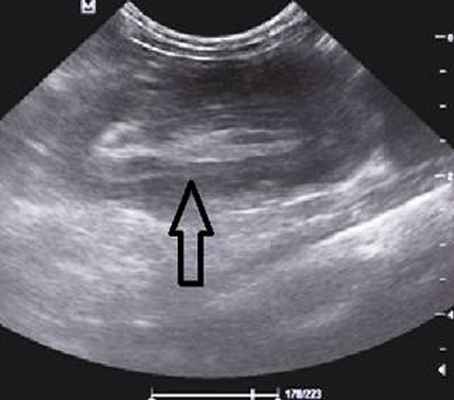

На рисунках 2 и 3 отображена ультразвуковая картина кишечной инвагинации.

Рис. 3. Симптом «псевдопочки»

В момент УЗ-исследования врач может определить один из симптомов:

- симптом "почки с завоздушенным центром".